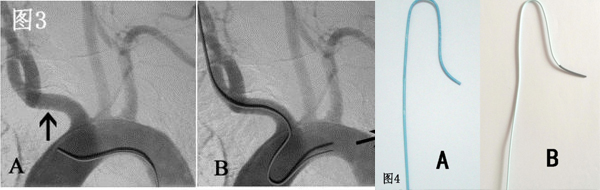

目前经桡动脉全脑血管造影通常选用的导管为西蒙造影导管,依据导管外形尺寸的大小分为三种型号,其中II-III型管均可被用于经桡动脉全脑血管造影(图4 A、B)。 西蒙造影导管的形状是按照经股动脉入路设计的,第一个弯在导管远端越过主动脉弓后可骑跨在主动脉弓上作为支点,而第二个弯曲则引导导管头端向上翘起,可选择性的进入无名动脉、左颈总动脉或左锁骨下动脉其中的任何一支血管(图3A)。 但是,在经桡动脉入路时,导管的第一弯曲无法骑跨在主动脉弓上,导管的第二弯曲引导的导管末端方向向下,这与脑主要血管的开口方向相反(图3B)。